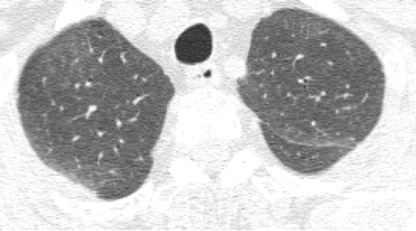

HRCT既可以表现为非纤维化型HP的特征,即片状或弥漫性磨玻璃影、不规则的小叶中央型结节、马赛克征、气体陷闭;也可能会表现为纤维化型HP的特征,即小叶间隔增厚、牵拉性支气管扩张、蜂窝肺、肺囊腔。

在最新的共识中提到了,典型的非纤维化型HP包含了两部分征象,一部分是肺实质浸润征象(磨玻璃影、马赛克影),一部分是小气道疾病征象(小叶中央型结节、气体陷闭)。非纤维化型HP也可能出现一些非特异性类型,除了磨玻璃影以外,还可以出现气腔实变、肺囊腔。

其中,马赛克影(Mosaic attenuation)是我们印象比较深刻的,马赛克影的识别通常是凭借吸气相CT,它既可以代表血管疾病,也可以代表气道疾病、间质性磨玻璃影、肺泡浸润等等。

从这张图片上,我们看到两种密度,高密度的是磨玻璃影,而低密度可能是正常的肺组织,也可以是由于小气道疾病引起的。

这是另外一个例子,双肺有斑片状的磨玻璃影,同时看到了有少量囊腔,还看到了正常密度的肺脏,双下肺靠近胸膜的地方有少量实变。